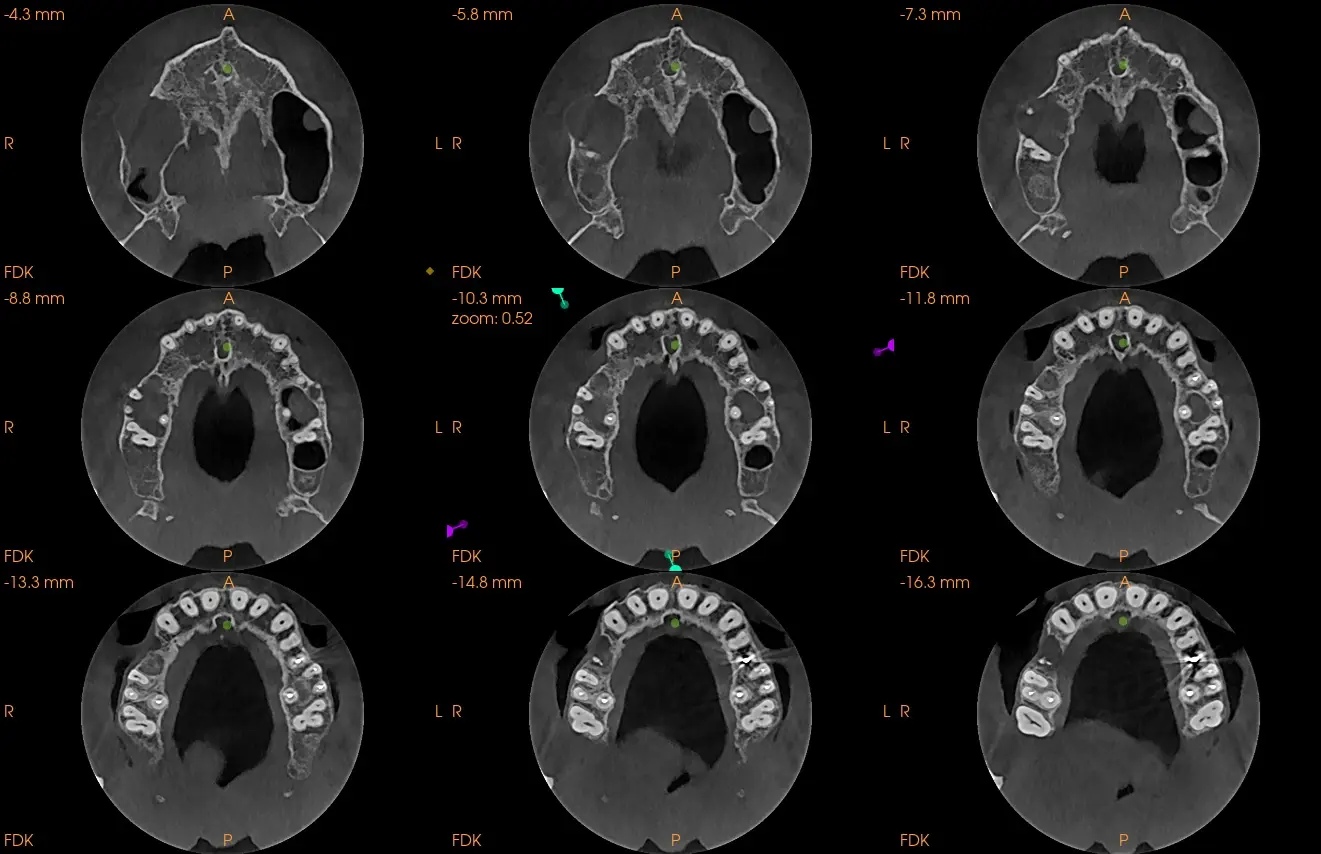

Estudio solicitado: Tomografía Cone Beam de un maxilar completo

Al realizarle la tomografía se evidencia de manera general dientes con tratamientos de conductos que no llelgan al limite CDC (Ver imagen 1 panorámica). En zona de Pd 16 se ve imágen hipodensa , de carácter expansivo que empuja las zonas adyacentes y el seno maxilar, generando una disminución del reborde óseo tanto palatino como vestibular, se observa que la pieza dental 16 presenta tratamiento de conducto, esta lesión genera también un engrosamiento de la membrana sinusal (posible quiste de retención mucosa) y disminución o posible ausencia del piso sinusal. Sobre la misma se observa en la imagen N°6 que presenta los cortes trasnaxiales, una cavidad de aire en dicho quiste periapical. Posiblemente debido a una interacción con las bacterias sinusales. En la cavidad sinusal se observa el pólipo sinusal de la cavidad derecha.

También en zona hemimaxilar izquierda se descubrió una lesión periapical en pieza dental 26, la raíz vestibulo mesial. que genera un leve engrosamiento de la membrana sinusal y fenestracion de tabla vesticular. (imagen 5)